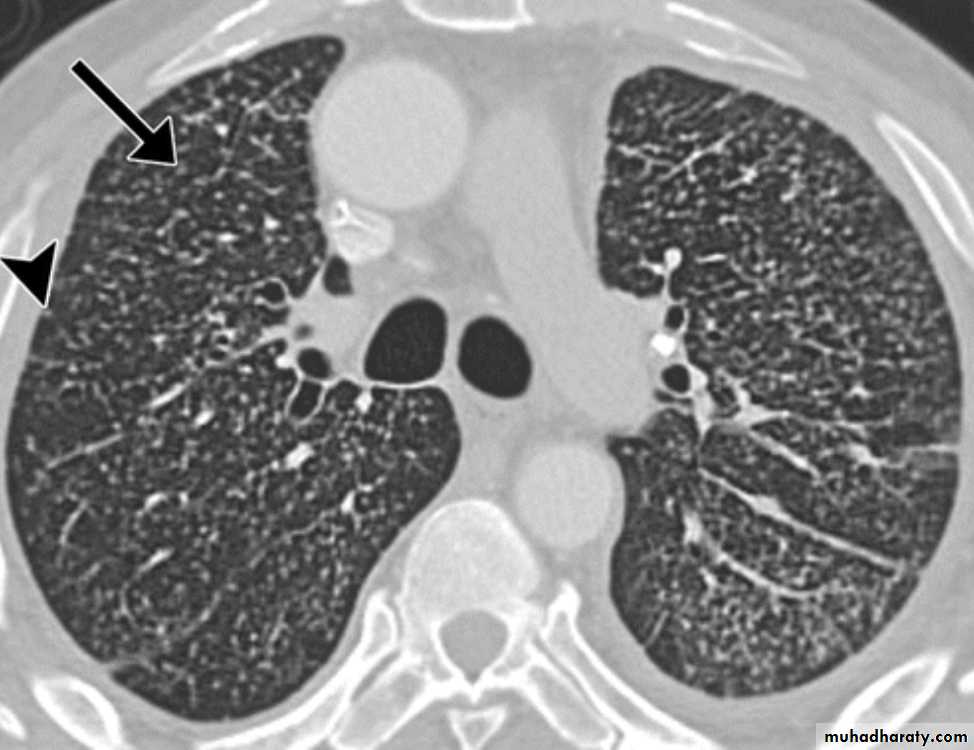

1- Miliary tuberculosis with multiple tubercles in numerous organs & tissues.2- Isolated metastatic organ lesions e.g., in kidney, bone, vertebra, joint & epididymis.

Few may spread into the body forming progressive primary TB.Secondary TB

Either occurs as a reinfection by mycobacterium TB or reactivation of primary infection when there is impairment in the immunity of the patient.Grossly: usually occurs at the apex of the lung with minimal lymph node involvement. There is marked damage in the lung parenchyma with cavity formation

Microscopically: Epitheloid granulomas with central necrosis & cavity.

Healing by fibrosis or may spread forming progressive secondary TB

* or enter through bronchial tree leading to tuberculous bronchopneumonia or spread into the pleural cavity leading to pleural effusion.

* or enter through the lymphatic channel or blood stream causing Miliary TB. or isolated organ TB.

X- ray,